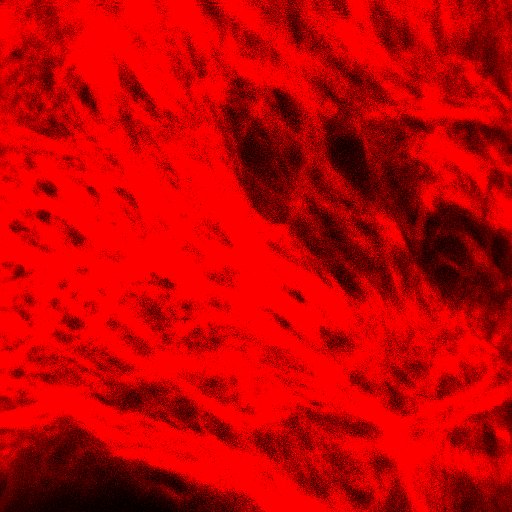

图6. 真皮层胶原纤维:纹理结构,呈现条带状或网状,采集时需注意到达此层若出现毛囊空洞需重新采集(以上双光子图源来自CIRS化妆品功效临床评价实验室)

- 可以在二次谐波通道观察到胶原纤维(红色),平面图像主要特征为纹理结构,呈现条带状或网状,立体图像由于不同深度的胶原纤维叠加,主要呈现为立体网状或蓬松的云状结构。